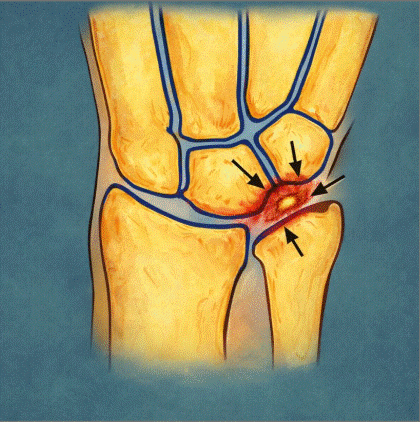

Tendinopatía rotuliana en deportistas: tratamiento y evidencia

La tendinopatía rotuliana en deportistas es una de las lesiones por sobrecarga más frecuentes y limitantes en los deportes que implican saltos repetitivos, como el baloncesto, el voleibol, el atletismo de saltos o el fútbol. Conocida popularmente como «rodilla del saltador», esta patología afecta al tendón rotuliano en su inserción en el polo inferior de […]